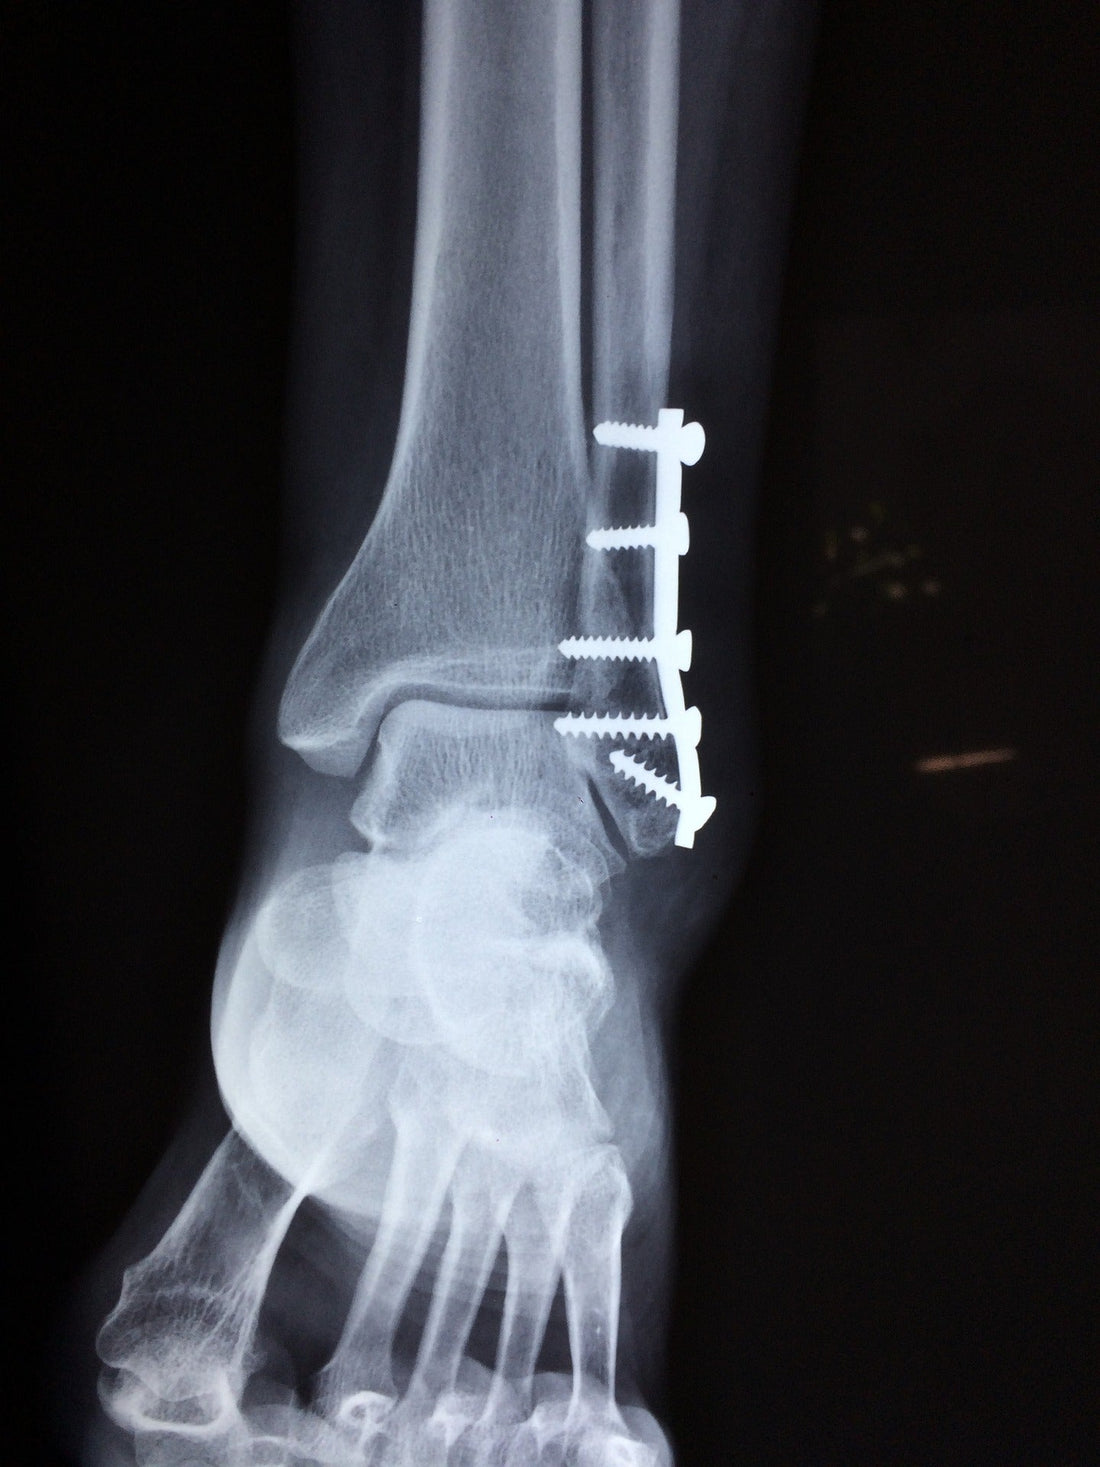

• Ankle fracture surgery - The broken bone fragments are moved back to the correct position inside the ankle and stabilizing items, such as screws and metal plates, are inserted to support correct healing.